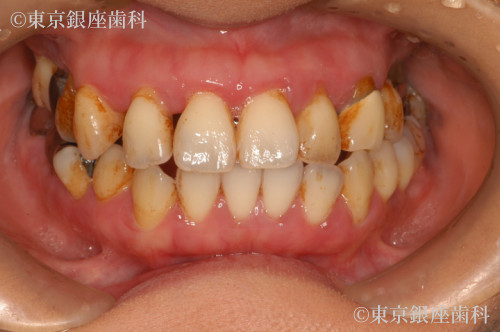

若くして重度歯周病に悩み上下インプラントで改善した40歳代女性の症例

Before

疾患 歯周病

長年歯周病に悩み、不安を抱えて来院。上下インプラントで噛み合わせと見た目が改善。術後調整を経て安定し、現在もメンテナンス継続中。